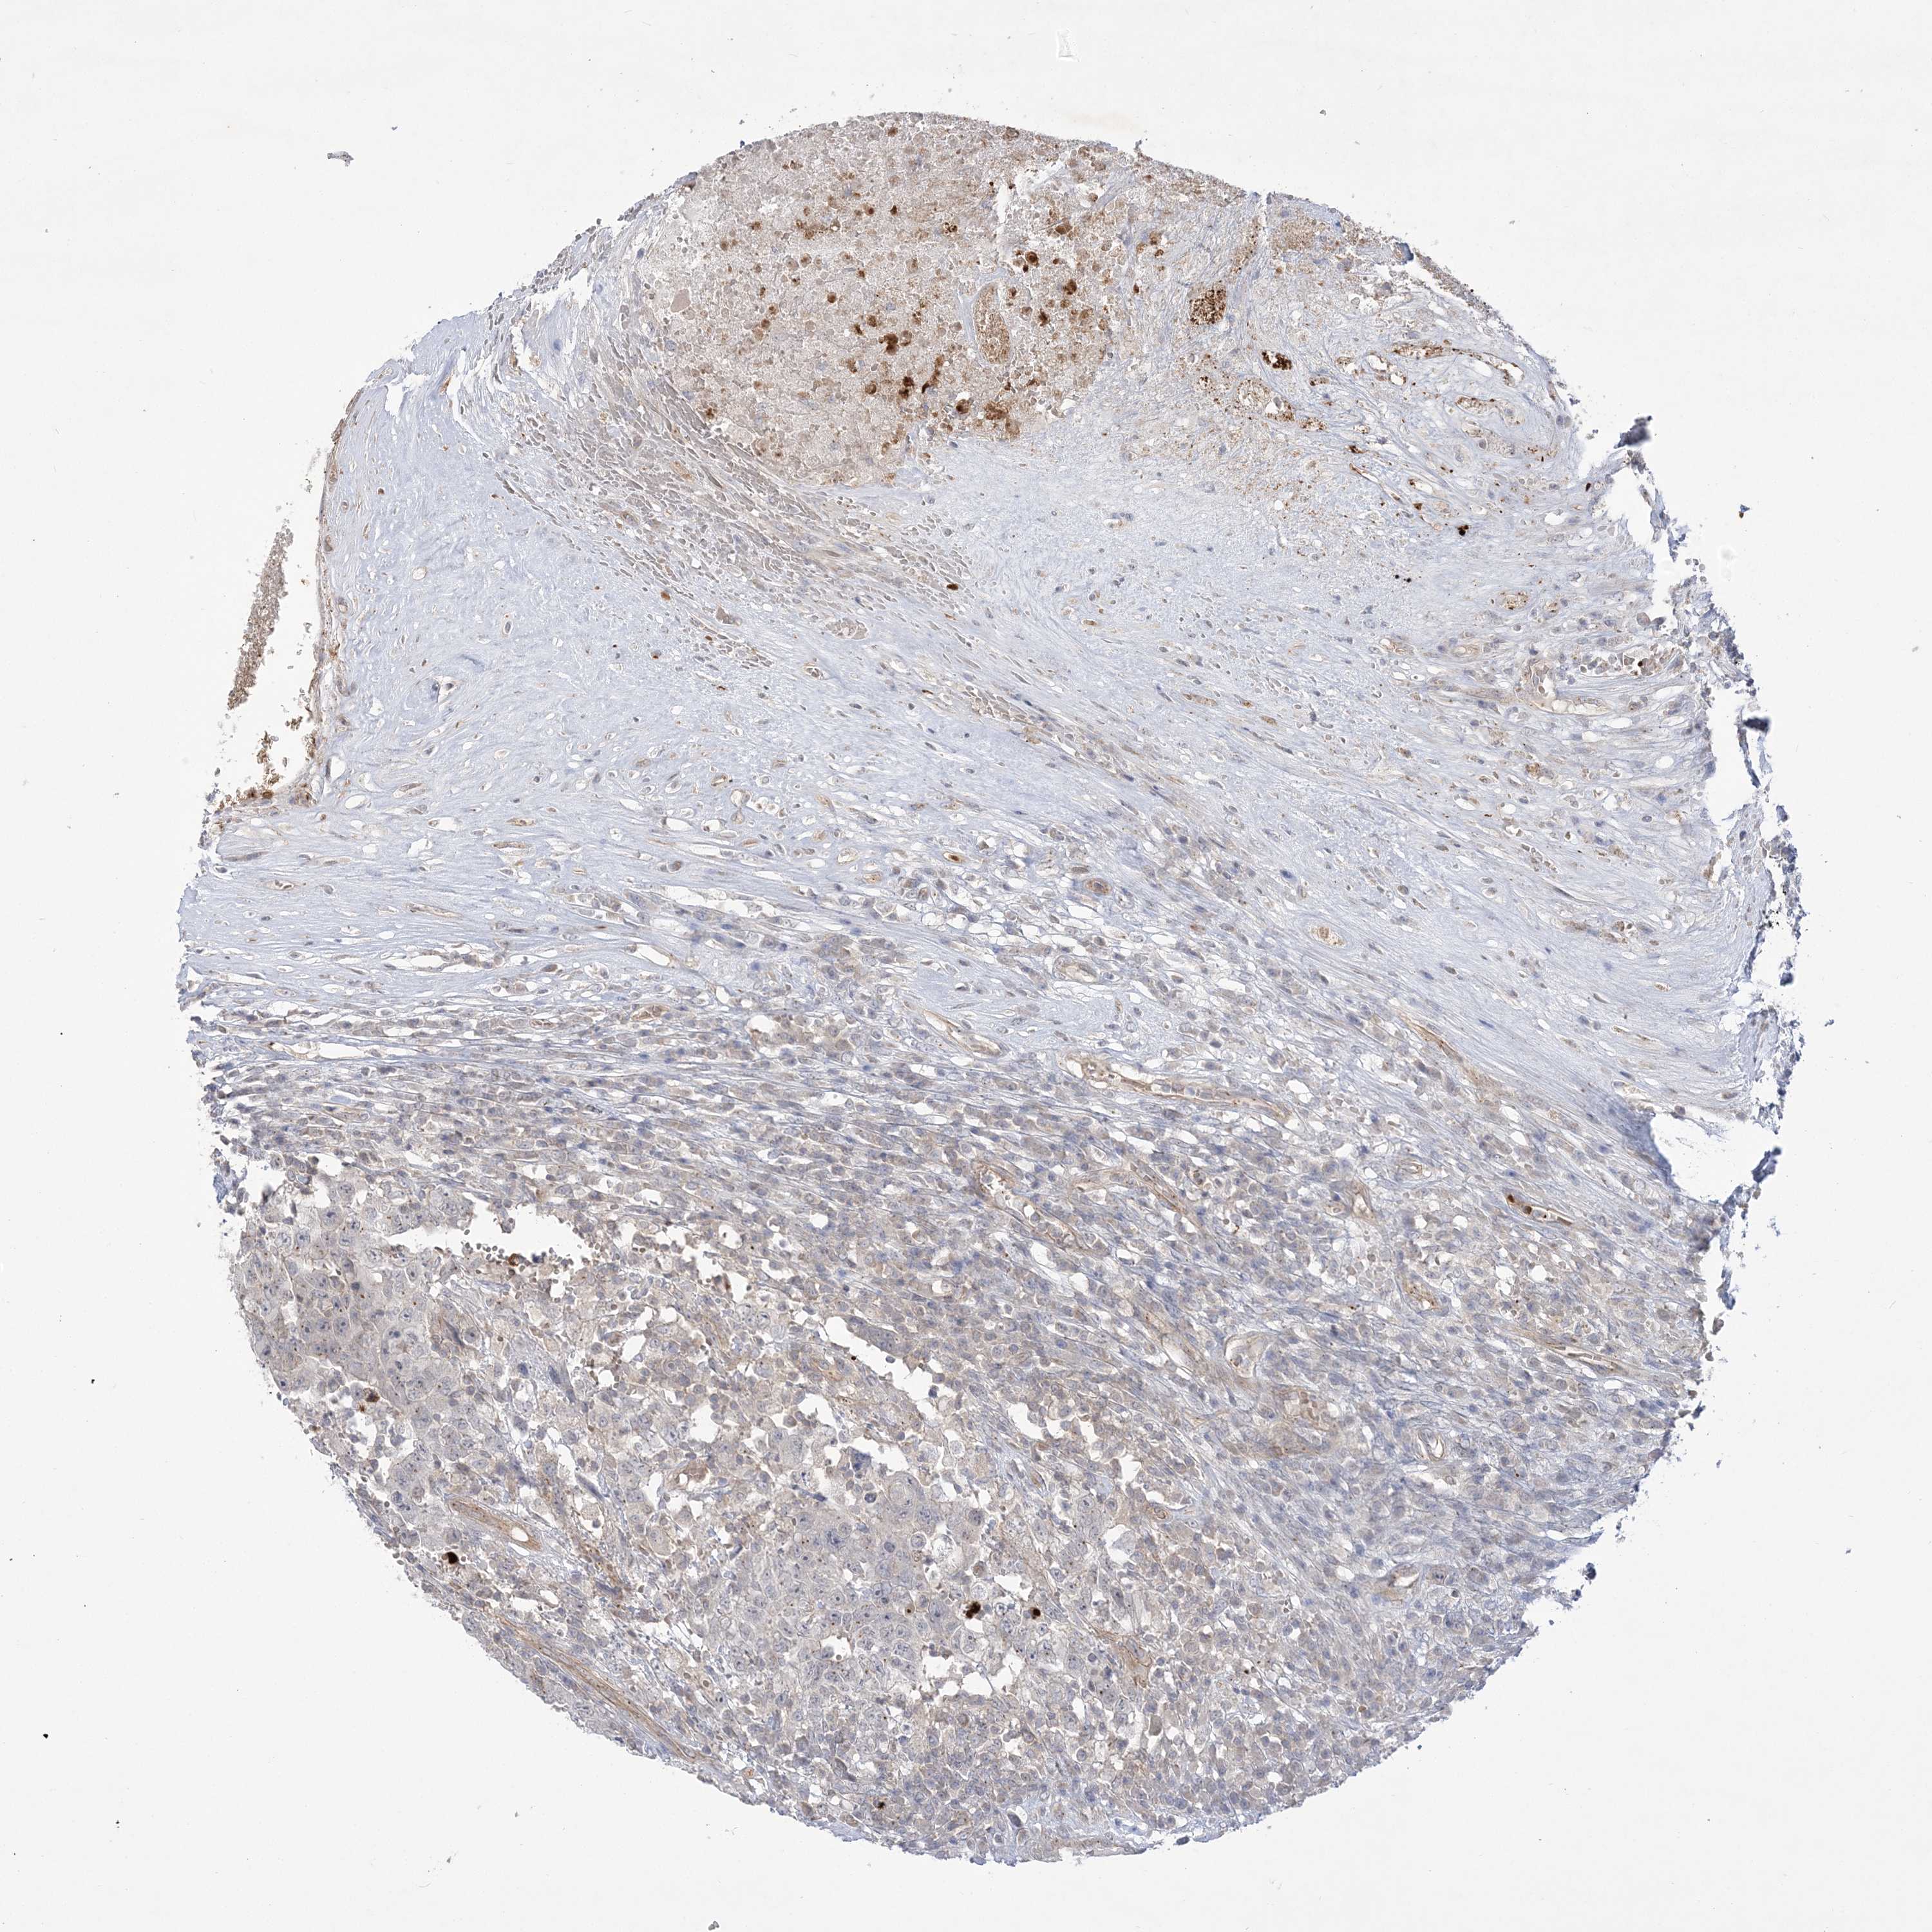

TESTIS CANCER - Protein expressioni

A mouse-over function shows sample information and annotation data. Click on an image to view it in a full screen mode. Samples can be filtered based on level of antibody staining by selecting one or several of the following categories: high, medium, low and not detected. The assay and annotation is described here.

Note that samples used for immunohistochemistry by the Human Protein Atlas do not correspond to samples in the TCGA dataset.

Antibody stainingi

Antibody staining in the annotated cell types in the current human tissue is reported as not detected, low, medium, or high, based on conventional immunohistochemistry profiling in selected tissues. This score is based on the combination of the staining intensity and fraction of stained cells.

Each image is clickable and will lead to virtual microscopy that enables deeper exploration of all samples and also displays staining intensity scores, fraction scores and subcellular localization as well as patient and tissue information for each sample.

Antibody HPA035973

Staining

High

Medium

Low

Not detected

Intensity

Strong

Moderate

Weak

Negative

Quantity

>75%

75%-25%

<25%

None

Location

Nuclear

Cytoplasmic/membranous

Cytoplasmic/membranous,nuclear

Carcinoma, Embryonal, NOS

Seminoma, NOS